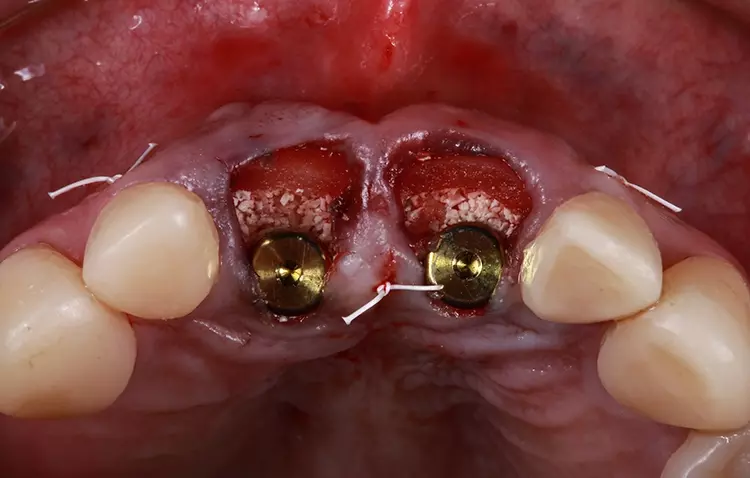

Die Bohrschablone wurde additiv aus speziellem 3D-Druckharz (Cosmos SG, Yller) auf einem Photon Mono 4K (Anycubic) hergestellt. Die Zähne wurden atraumatisch unter Erhaltung der Integrität der Gingiva und der Gingivaarchitektur extrahiert (Abb. 11).

Basierend auf dem klinischen Befund einer Grad-3-Mobilität und den röntgenologischen und computertomografischen Befunden einer Wurzelresorption und postendodontischer periapikaler Granulome wurde entschieden, beide mittleren Schneidezähne zu extrahieren und durch Implantate zu ersetzen. Der Verlust der vertikalen Dimension der Okklusion und die fehlende anteriore Führung würden die sofort belasteten Implantate gefährden. Aus diesem Grund wurde die Stabilität der Okklusion vor dem chirurgischen Eingriff wiederhergestellt.